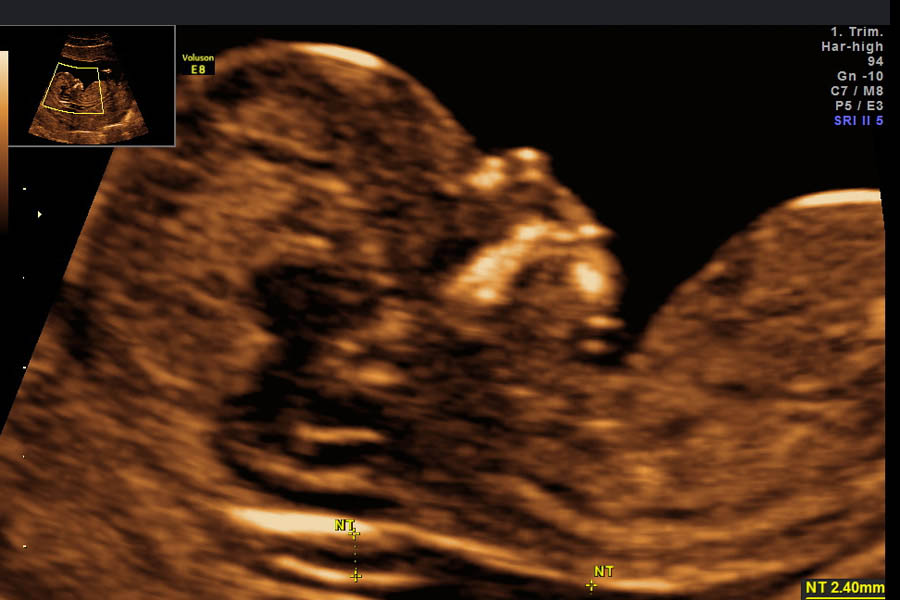

Mithilfe des Ultraschalls wird beim ungeborenen Kind ein Flüssigkeitssaum im Bereich des Nackens gemessen, der als Nackentransparenz (NT) bezeichnet wird. Darüber hinaus gibt es noch zusätzliche UltraschalImarker, die auch im praenatarium dargestellt werden, wie z.B. das Nasenbein, oder der korrekte Klappenschluß in der rechten Herzkammer.

Die Nackentransparenzmessung kann Hinweise darauf geben, ob ein Fetus möglicherweise eine Chromosomenveränderung wie Trisomie 21 oder Trisomie 13/18, und/oder einen Herzfehler hat. Falls die Nackentransparenz verbreitert ist, muss nicht unbedingt ein gesundheitliches Problem bestehen. Auch gesunde Kinder können im ETS mit einer verbreiterten Nackentransparenz auffallen.